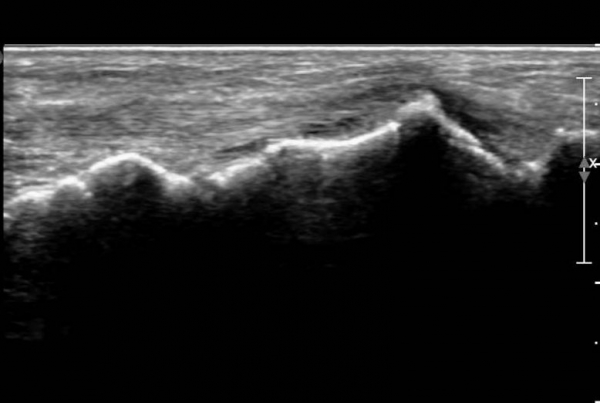

ÃÊÀ½ÆÄ ¼Ò°ß :  Àü°æ°ñ°Ç Á¾´Ü¸é°Ë»ç¿¡¼­ Àü°æ°ñ°ÇÀÌ °í¿¡ÄÚ¼¶À¯È­(hyperechoic fibrillar pattern) ¾ç»óÀ¸·Î °üÂûµÇ´Âµ¥

¼³Çü°ñ ºÎÂûºÎ¿¡¼­ °æ¹ÌÇÑ Á¦¿¡ÄÚ ¾ç»óÀÌ °üÂûµÈ´Ù(»çÁø 1, 2).